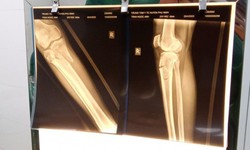

Bị tai nạn giao thông, cụ ông 71 tuổi gãy xương cẳng chân phức tạp

Camera bệnh viện - 11/05/2023 09:21SKĐS - Nhập viện trong tình trạng gãy vỡ mâm chày thành nhiều mảnh phức tạp, trên nền bệnh huyết áp cao, tiểu đường tuýp II, bệnh nhân đã được phẫu thuật kết hợp xương cẳng chân.